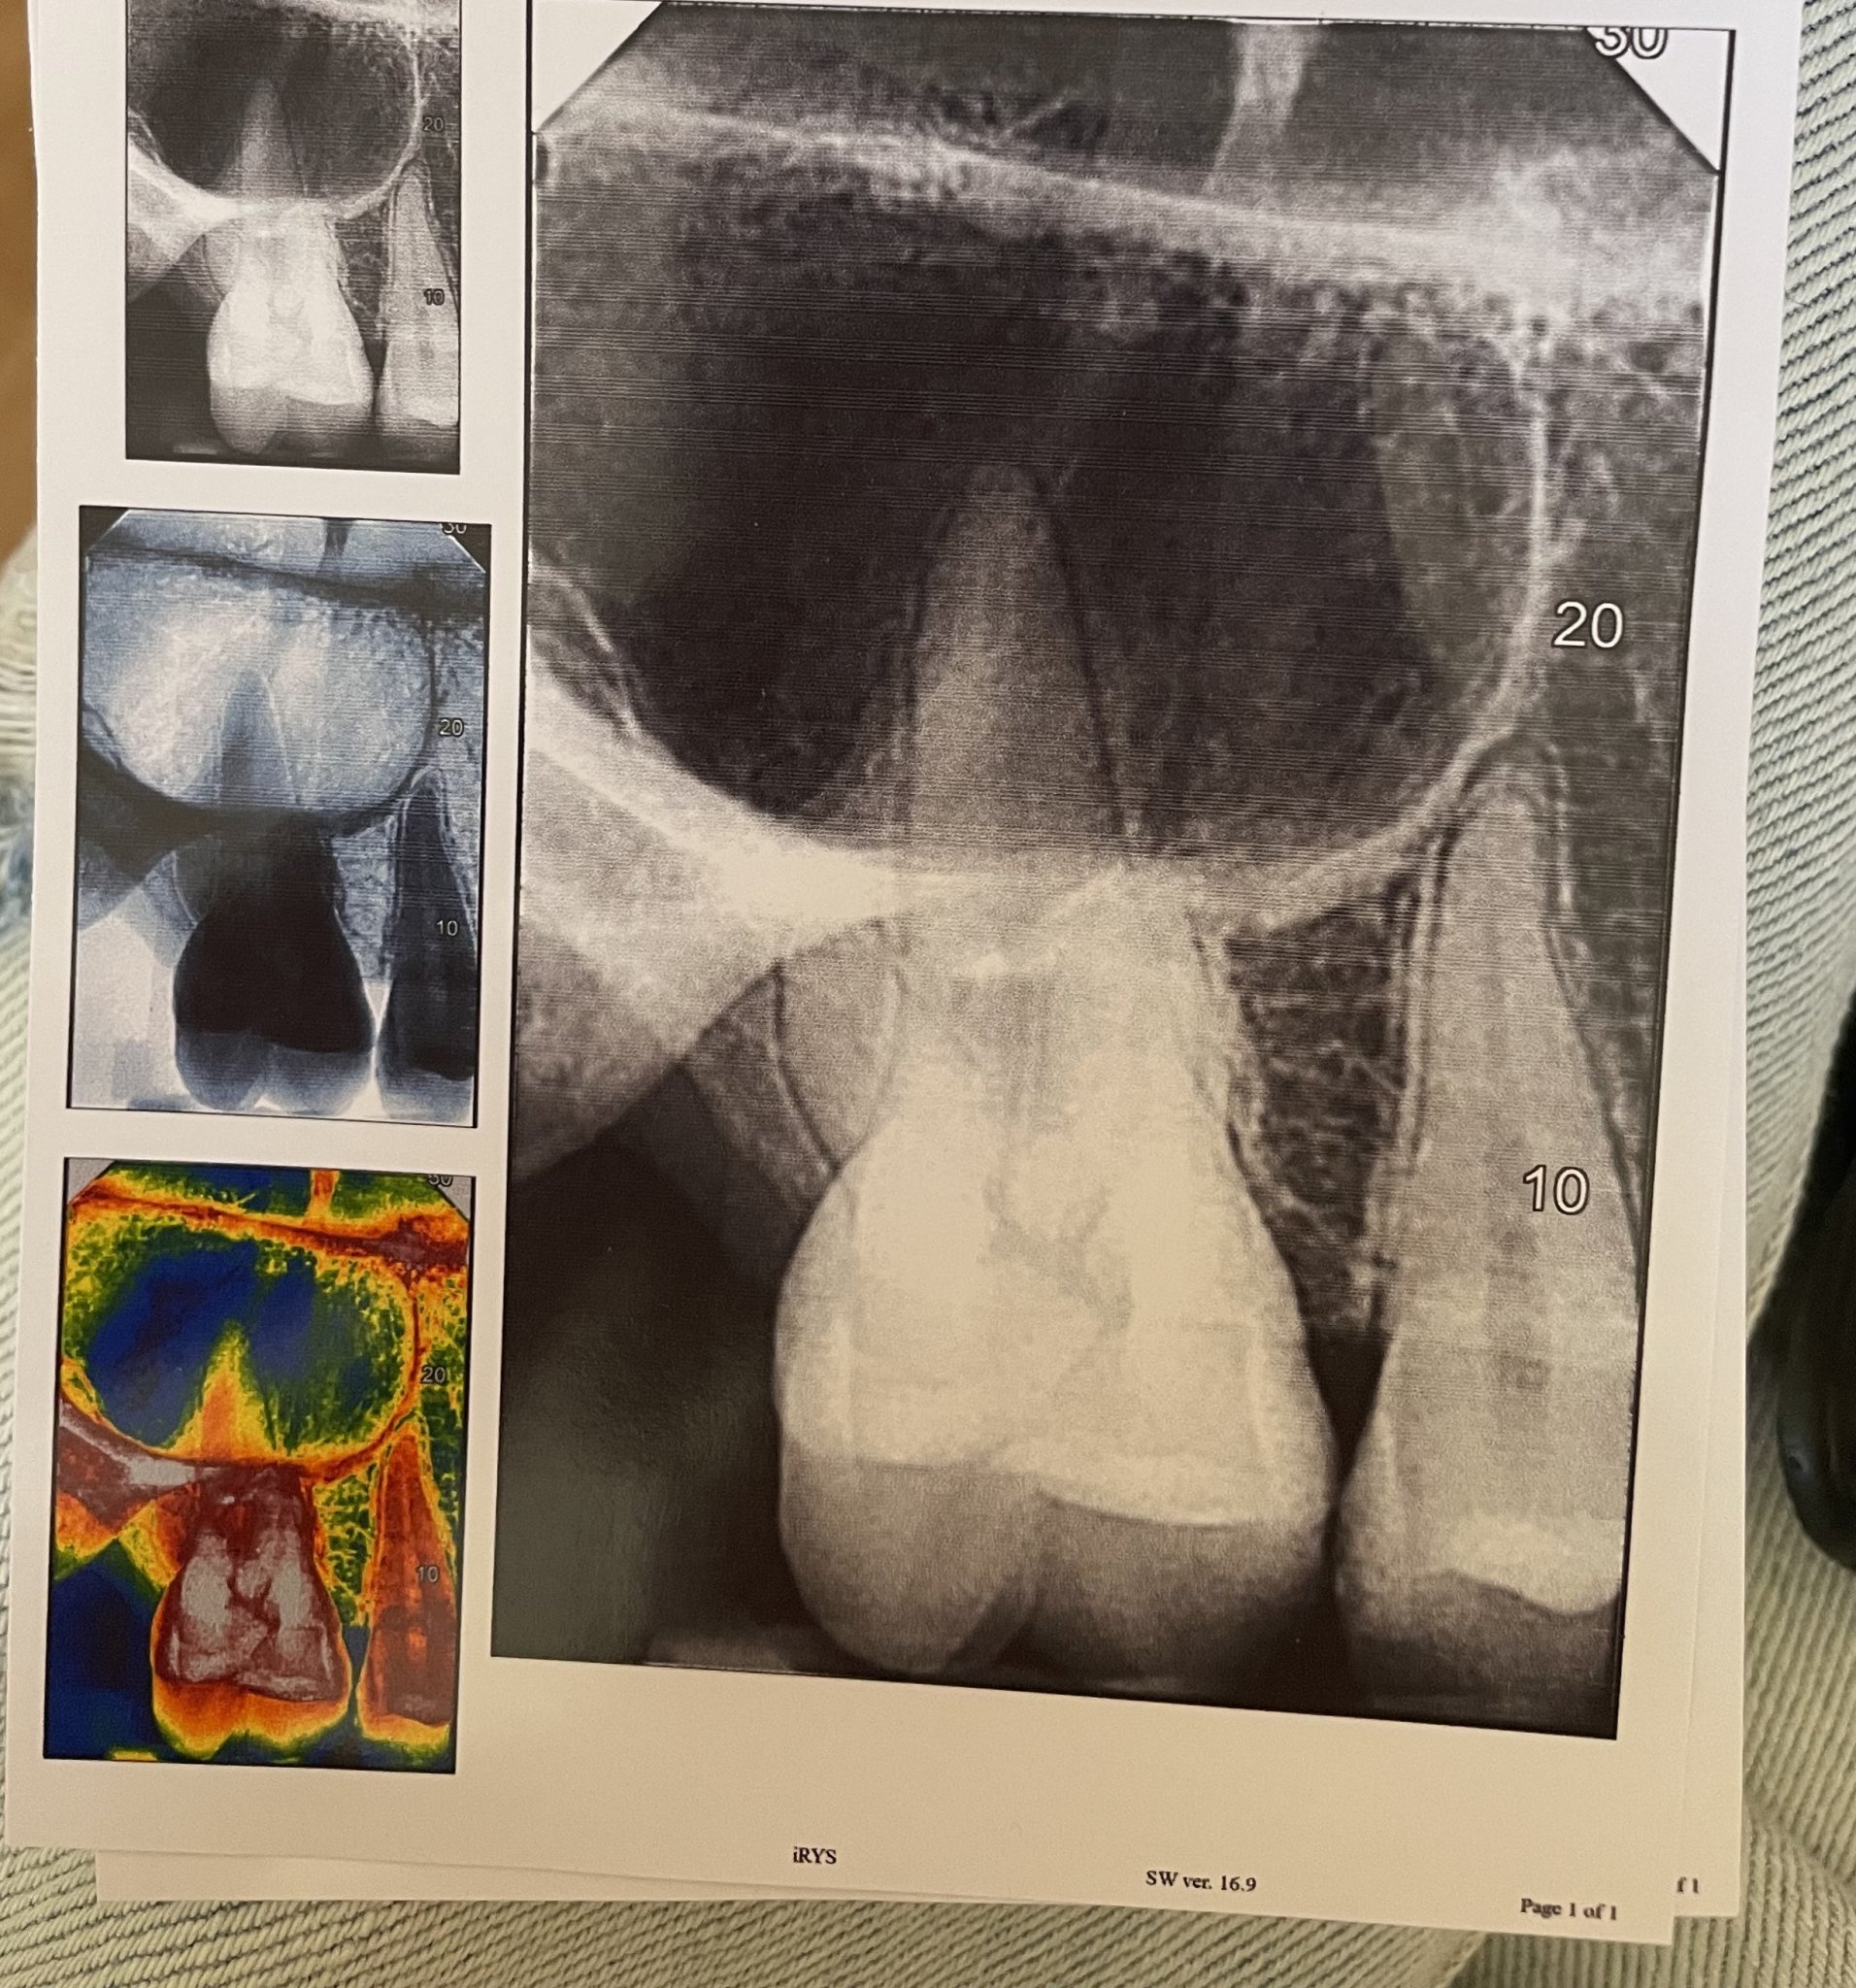

.   Много Ви благодаря за отговора.Днес правих снимка на изваденият зъб и на друг зъб от другата страна ,където също имам болка и чувствам ,че е от зъб.Бихте ли помогнали с разчитането на снимкте?